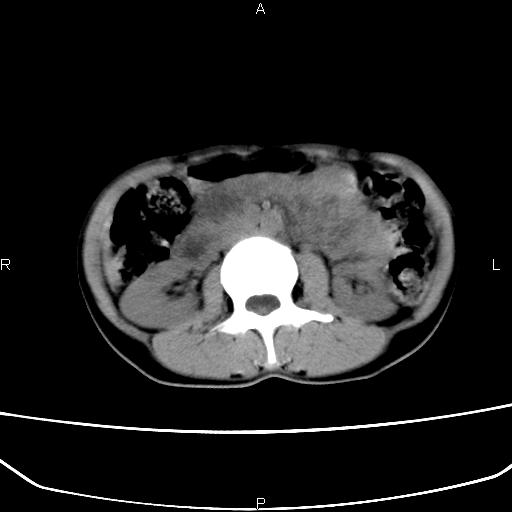

患者女40岁,自诉近半年来感觉上腹部疼痛,饱胀感。大便青黑色。曾做胃镜示浅表性胃炎。无其他病史。

腹膜后多发软组织密度影,考虑淋巴结转移。淋巴瘤不除外。

(1)胃ca并腹膜后淋巴转移(2)脾大

胃癌在哪?腹膜后淋巴结肿大,胰腺可疑。

胃明显扩张,十二指肠降部及水平部显明不清,腹膜后淋巴结肿大,考虑十二指肠肿瘤性病变。